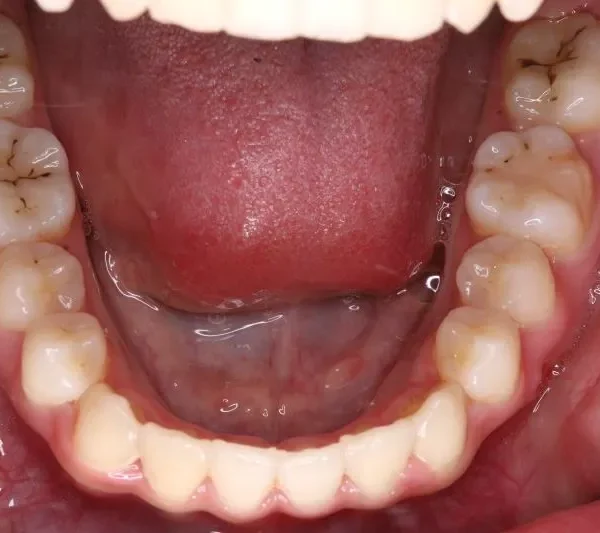

• 初診

初診

状態 ガタガタ・でこぼこに生えている(叢生)

受け口(下顎前突/反対咬合)

前歯で噛めない(開咬/オープンバイト)

上下前歯、口元が出ている、口ゴボ(上下顎前突)